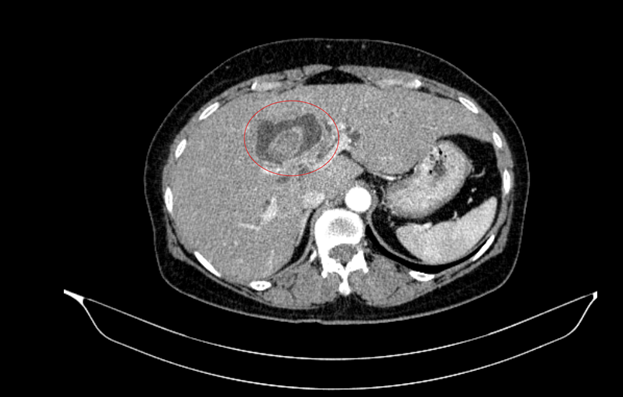

Bệnh nhân nữ, 59 tuổi, nhập viện trong tình trạng vàng da, ngứa và đau vùng hạ sườn phải kéo dài. Kết quả chẩn đoán hình ảnh cho thấy tổn thương đường mật trong gan kèm sỏi và giãn đường mật.

Hình ảnh sỏi đường mật tạo ổ áp xe gan - đường mật gan trái( vòng tròn màu đỏ). Giãn nhẹ đường mật trong gan hai bên. Dày thành nhẹ ngã ba đường mật trên phim chụp cắt lớp vi tính.